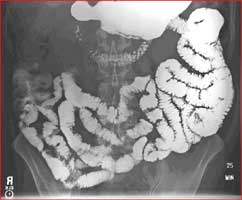

Small bowel follow-through

• Small Bowel Follow-Through: used to evaluate the small intestines after drinking oral contrast. The radiologist looks for cause of obstruction, inflammation, strictures, or masses.